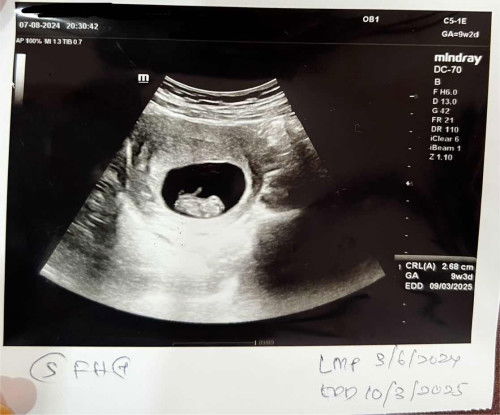

Scan pregnancy 9w2d

Semalam scan early pregnancy at 9w2d. Alhamdulillah semuanya normal. Saiz baby besar 9w3d. Semoga membesar dengan baik dan sempurna 🥹